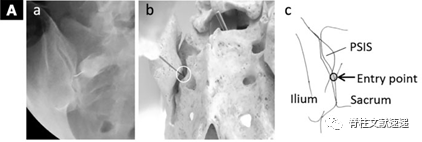

②   进针点位于髂后上棘与骶骨外侧嵴边界的平行线相交点,方向几乎是垂直透视角度进针。针刺处局部麻醉,23或22号长度90.0mm的穿刺针,插入关节中间部分,也就是之前说的第2区域。

③   进针过程中遇到骨组织,此时调整透视机角度,尾倾25-30°。此时能清晰显示骶骨与髂骨之间的间隙。

④   调整针的方向至关节后缘,继续进针至髂骨壁中部,回抽,此时由于软骨的存在,有时会有堵塞感,注射造影剂时适当退回针头。然后注射造影剂充满关节腔,再注射1.5-2.0ml2%的利多卡因。